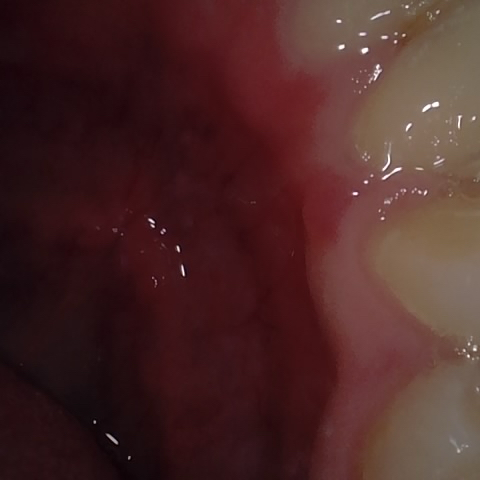

Annotated as "Bad"